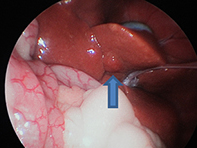

上の写真のようにトロッカーを挿入しカメラを挿入すると、右のように肝臓は瀰漫性に変色していました。 もうひとつトロッカーを挿入し、バイオプシー鉗子にて採材しました。 また肝硬変の可能性があったため、経脾的門脈造影も行ない、Cアームにて確認、異常がないことも確認致しました。

この子は『軽度肝硬変』と診断され、適切な内科療法により、元気に過ごしています。